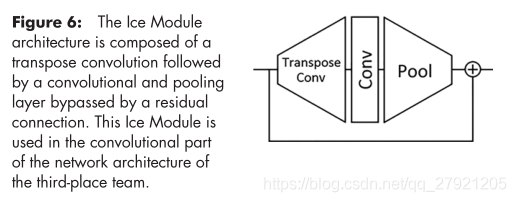

提出了新的模块Ice module: